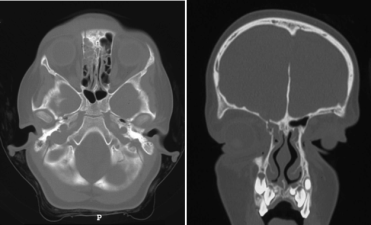

l’os du crâne de l’enfant possède une certaine élasticité, ce qui n’est pas le cas de la dure-mère qui tapisse sa face interne. on retrouve typiquement un recul notable du complexe médio-frontal

(disjonction orbito-naso-ethmoïdo-frontale) avec fractures en bois vert des parois ethmoïdales, qui s’associent à une déchirure linéaire antéro-postérieure de la dure-

mère (Cf. ci-dessus) ; en effet, la dure-mère est très adhérente à l’os au niveau des sutures, notamment fronto-ethmoïdale, ce qui est illustré par les rares hématomes extra-duraux du toît d’orbite (Cf. ci-contre). en cas de fracture il y aura donc déchirure durale et non décollement en regard de la suture.

par ailleurs, la déchirure durale s’associe volontiers à une hernie cérébrale trans-durale qui empêche la cicatrisation méningée, mais colmate temporairement la brèche ostéo-durale (avec absence trompeuse de rhinorrhée cérébro-spinale). ces lésions de l’os, de la dure-mère et du cerveau sous-jacent peuvent évoluer sous forme d’une authentique fracture évolutive de la base du crâne.